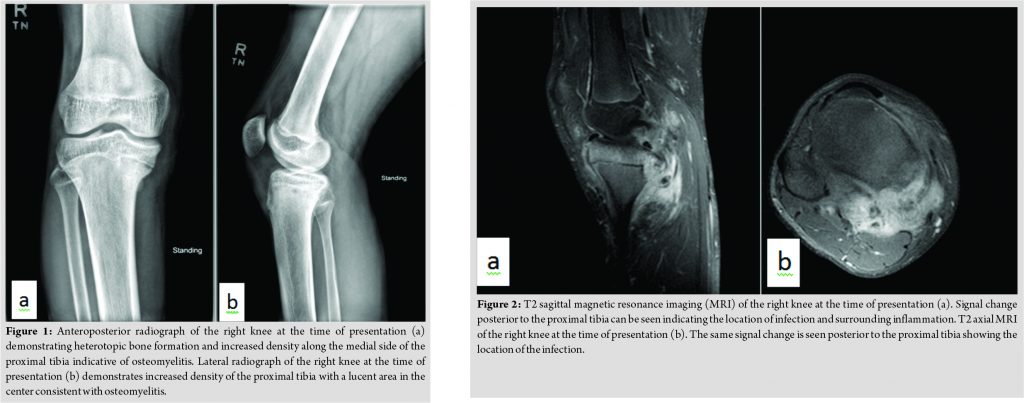

A 16-year-old previously healthy young man presented to the Pediatric Infectious Disease Clinic in September of 20151week after arriving in the United States from a refugee camp in Mozambique with a 3-month history of pain and swelling in the upper leg just below the knee. He had no fever noted, no erythema over the knee, and his symptoms had not changed appreciably since arrival in the United States. He had not received any antimicrobial therapy for this condition. His erythrocyte sedimentation rate (ESR) at presentation was 40 mm/h with a C-reactive protein (CRP) level of 0.9 g/dL and a leukocyte count of 6,900 cells/µL (50% polymorphonuclear cells, 37% lymphocytes, 11% monocytes, 1% eosinophils, and 1% basophils). On examination, his affected knee was slightly swollen with mild tenderness over the medial aspect. No discharge or erythema was noted. His range of motion for his knee was slightly decreased for flexion and extension, and an antalgic gait was present. At that time, a plain radiograph demonstrated concerns of chronic osteomyelitis of the right proximal tibia although tumor or subacute fracture was also considered (Fig. 1). Contrasted magnetic resonance imaging (MRI)demonstrated findings consistent with chronic osteomyelitis along the medial aspect of the proximal tibial epiphysis and metaphysis, however, with a cloaca extending from a cortical disruption of the posteromedial tibial metaphyseal cortex (Fig. 2).